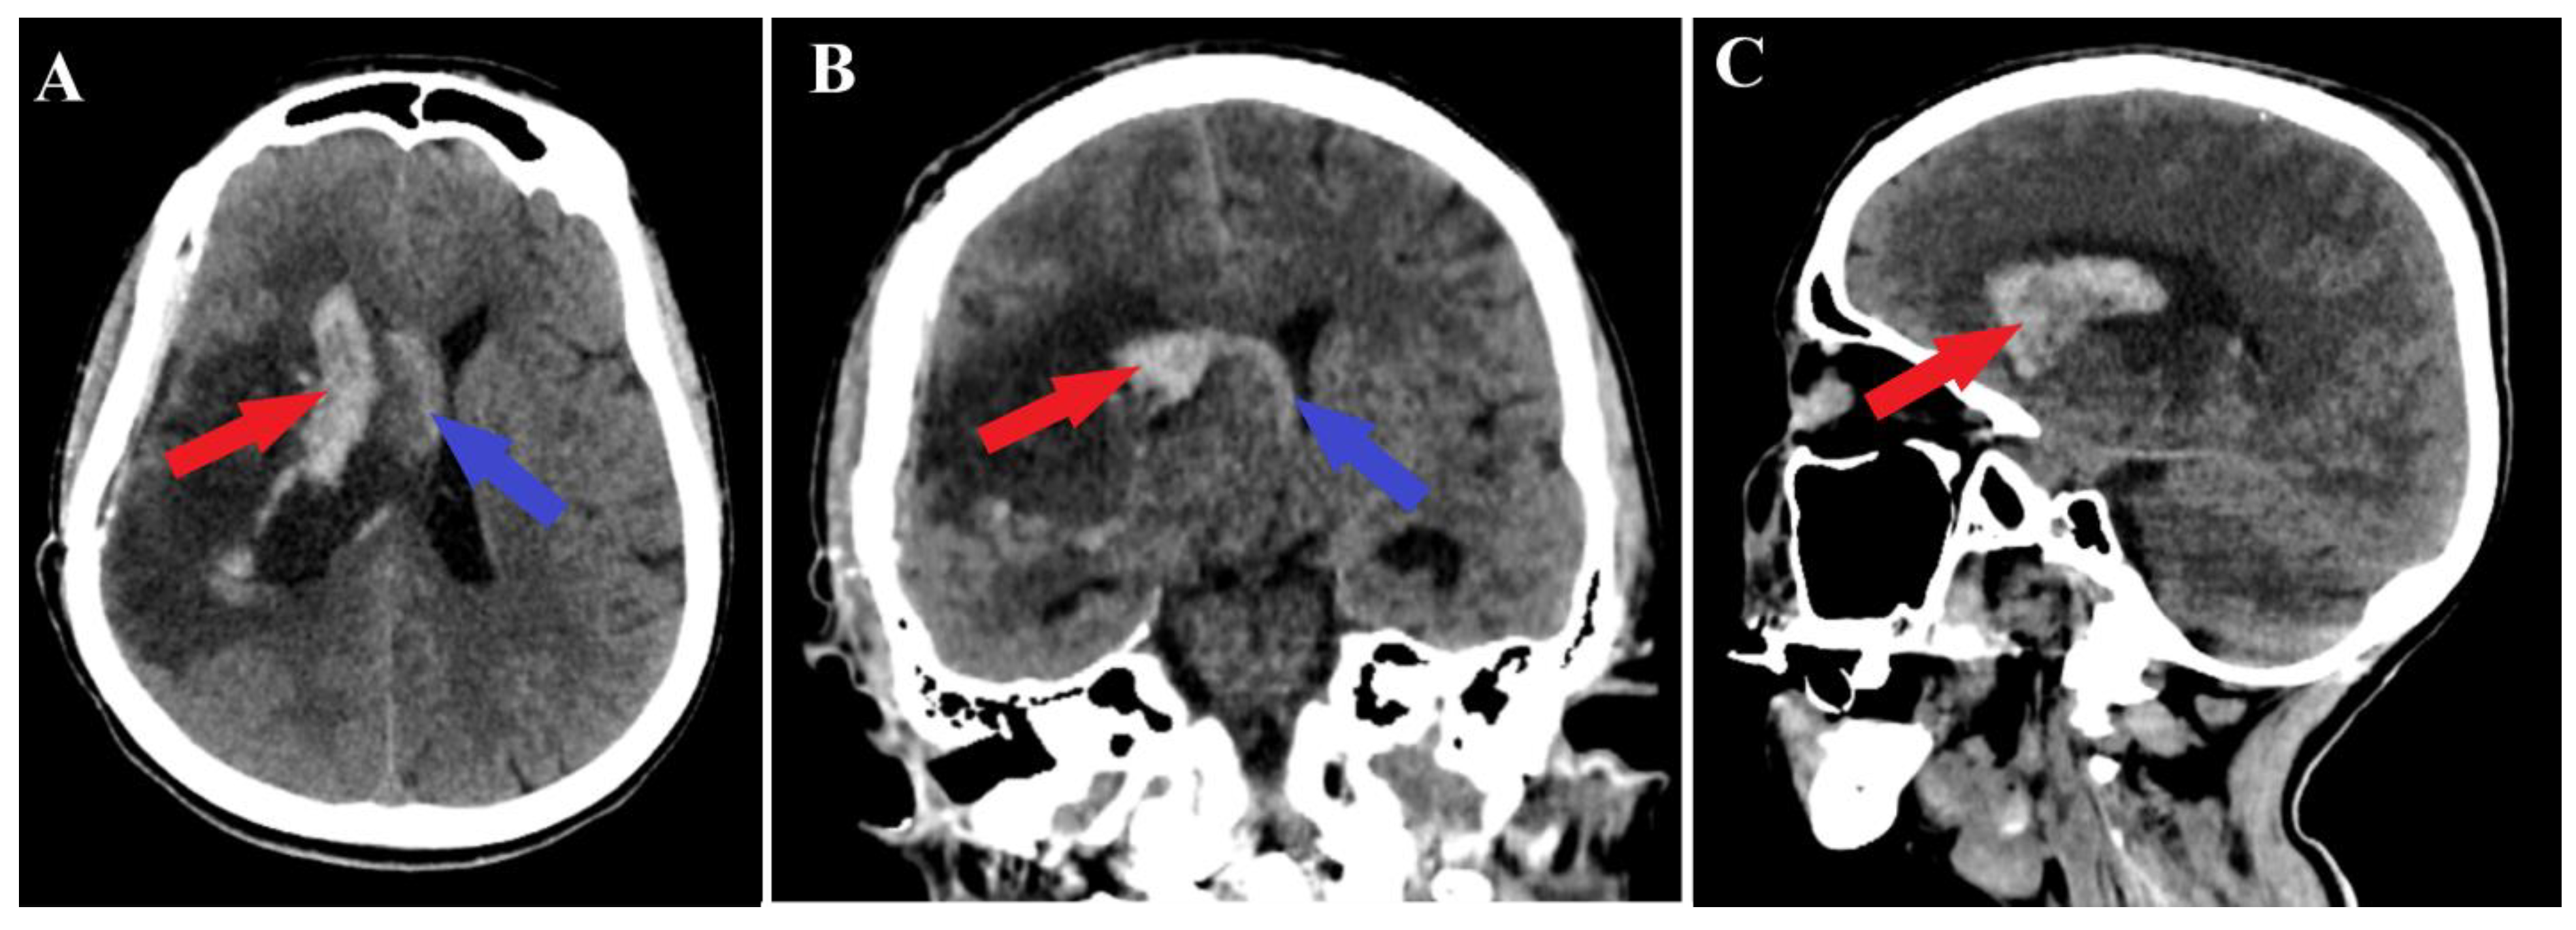

Figure 5.

Postoperative CT scan, hematoma. Those images (A—axial section, B—frontal section, C—sagittal section) show a persistent pan ventricular and intraparenchymal hematoma (red arrow), as well as the contralateral intraventricular infiltration of the hematoma (blue arrows).